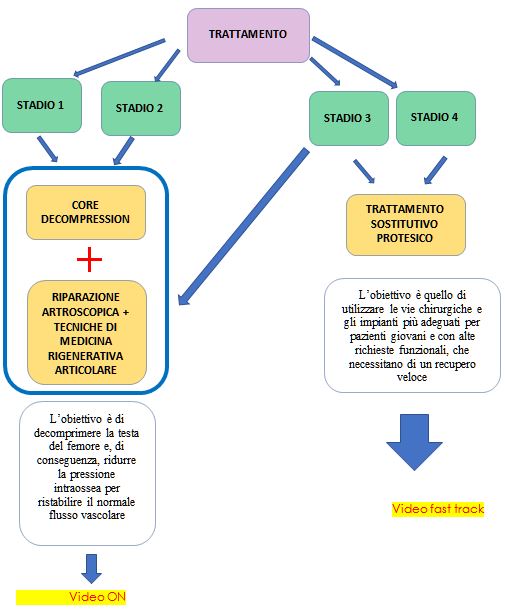

Le caratteristiche del paziente, le richieste funzionali e l’avanzamento della patologia stessa sono i fattori da considerare nella scelta terapeutica.

In particolare, lo stadio della patologia viene classificato secondo la classification de recherche osseous (ARCO) in 4 livelli basati su reperti radiografici e di risonanza magnetica.

L’approccio terapeutico può prevedere un trattamento incruento (farmacologico o biofisico) solo nelle fasi più precoci; più frequentemente risulta invece di tipo chirurgico.

In considerazione dell’età precoce in cui spesso la malattia si manifesta e, conseguentemente, delle elevate richieste funzionali, emerge l’importanza di opzioni terapeutiche “biologiche” che consentano di risparmiare l’articolazione, evitando il collasso dell’osso subcondrale.

Il trattamento richiede invece nelle forme più avanzate (STADIO 3 e 4) la sostituzione protesica dell’anca stessa.